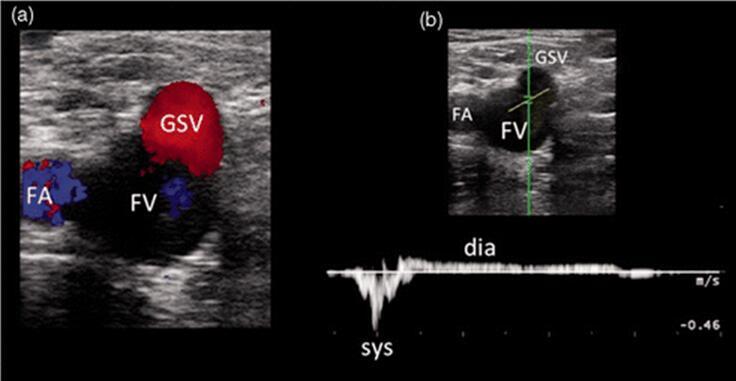

图18。SFJ隐股交界处功能不全。(一)隐股交界处在舒张期返流的彩色模式证据。(b)检测到PW返流。根据文献报道,超声探头务必要放在SFJ瓣膜的静脉端。FA,FV和GSV横截面形状形成所谓的米老鼠特征,是正确评价SFJ瓣膜完整性的位置。FA:股动脉;FV股静脉;GSV大隐静脉(大系统:sys:肌肉收缩;DIA:肌肉舒张。